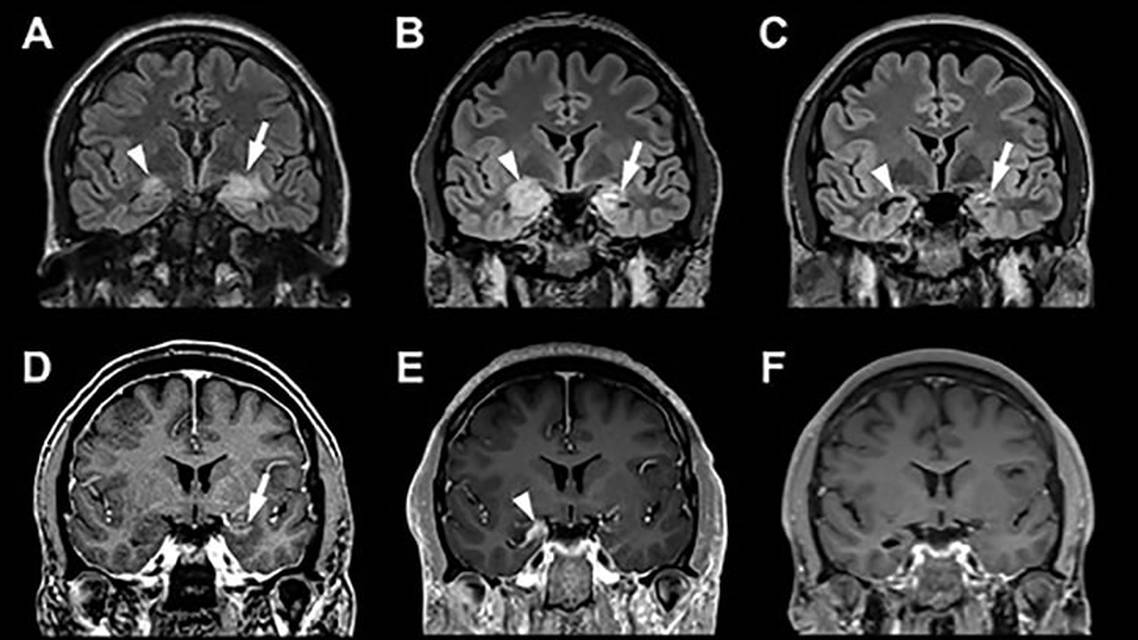

We present the case of Mr R who had a past medical history of testicular seminoma and presented with NORSE. He was treated with a 5-day pulse of IV methylprednisolone and discharged after clinical improvement of his seizures. Over the next 3 months, he developed worsening anterograde amnesia and a repeat brain MRI demonstrated worsening of T2 signal abnormality in the bilateral hippocampi. Retreatment with PLEX and IV methylprednisolone commenced, after which Mr R was discharged with maintenance oral steroid and mycophenolate treatment. He again improved, and steroids were tapered, but seizures returned and became refractory to multiple ASMs and immunotherapy. Mr R’s cognitive prodrome, history of testicular tumor, drug-resistant seizures, and antiMa2 seropositivity best fit the diagnosis of antiMa2-mediated AAE.